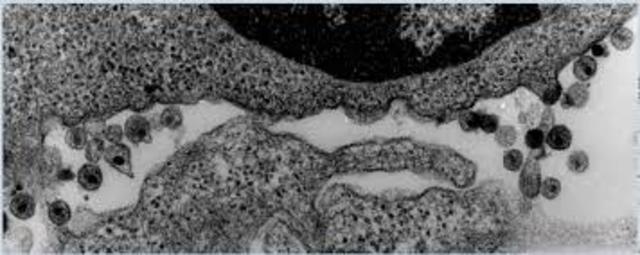

la el virus HIV en el Instituto Pasteur (Francia) y en el Instituto Nacional de Salud (Estados Unidos).